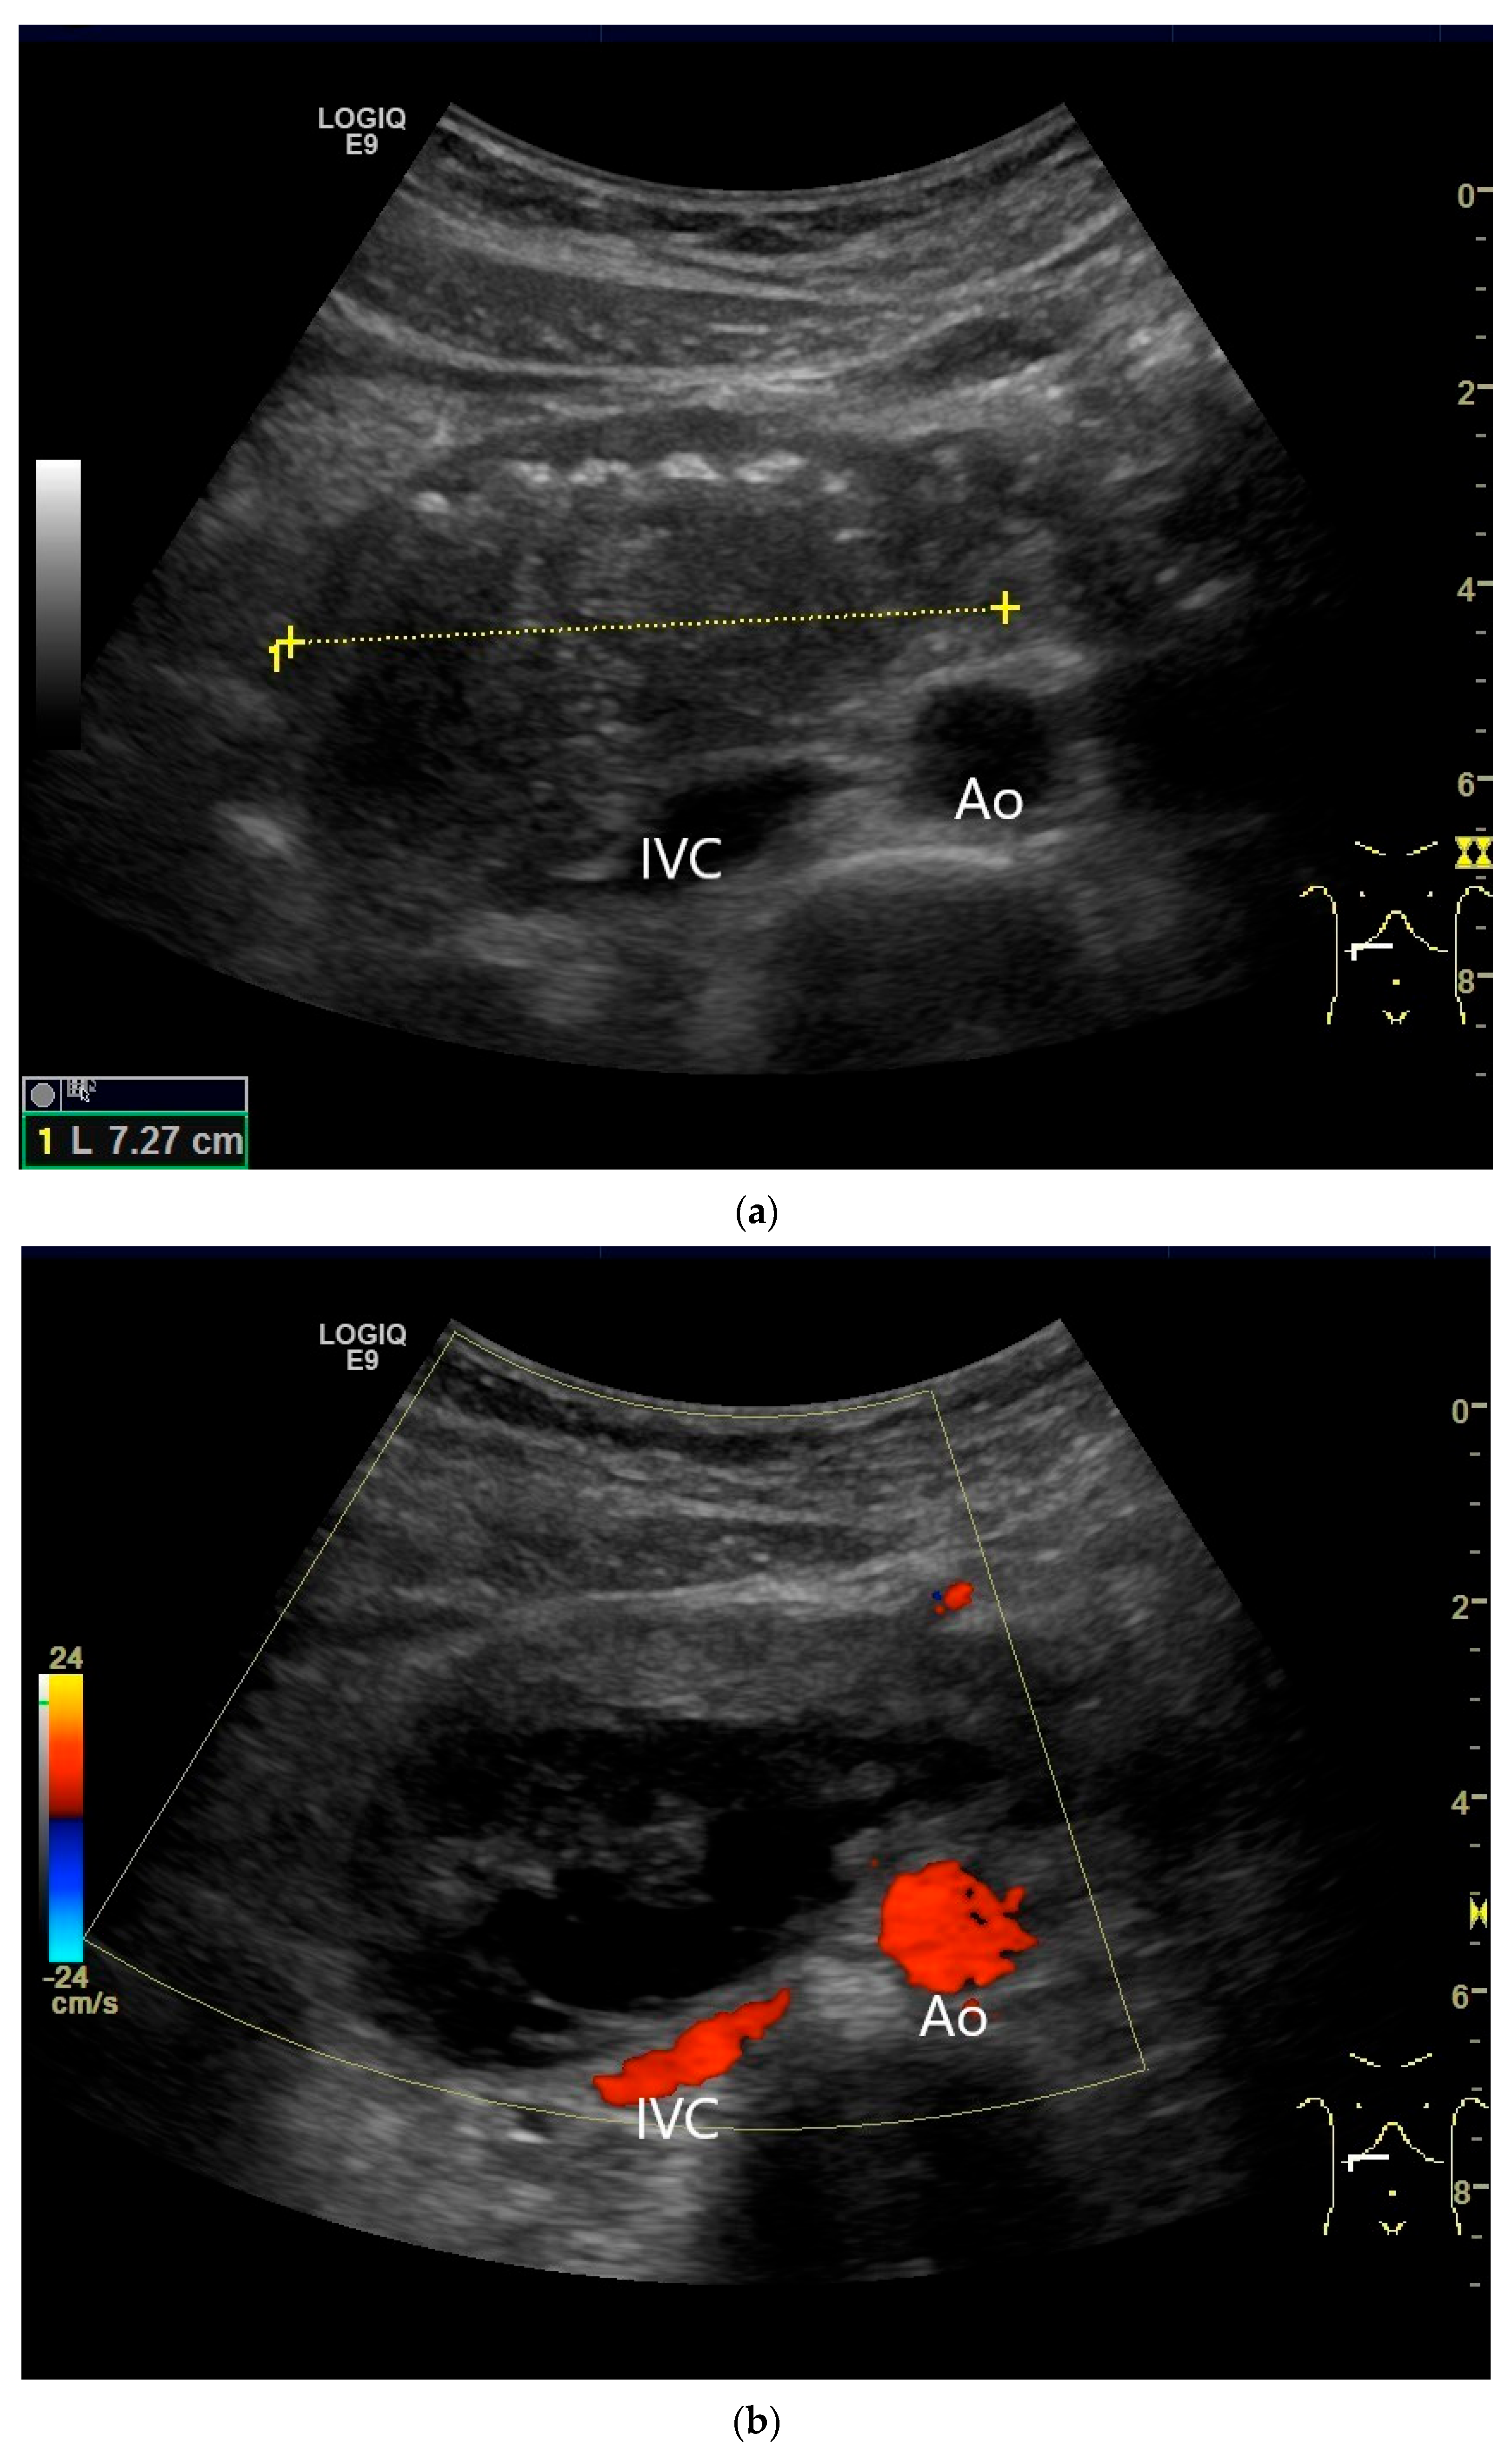

- Smereczyński, A.; Starzyńska, T.; Kołaczyk, K. Mesenteric changes in an ultrasound examination can facilitate the diagnosis of neuroendocrine tumors of the small intestine. J. Ultrason. 2015, 15, 274–282. [Google Scholar] [CrossRef]

| Neuroendocrine tumor | Small, nodular hypoechoic wall thickenings, mostly in the submucosa with spreading into the other layers. Usually with small vessels on CDI. Regionally enlarged lymph nodes. Multilocular manifestations are possible. |